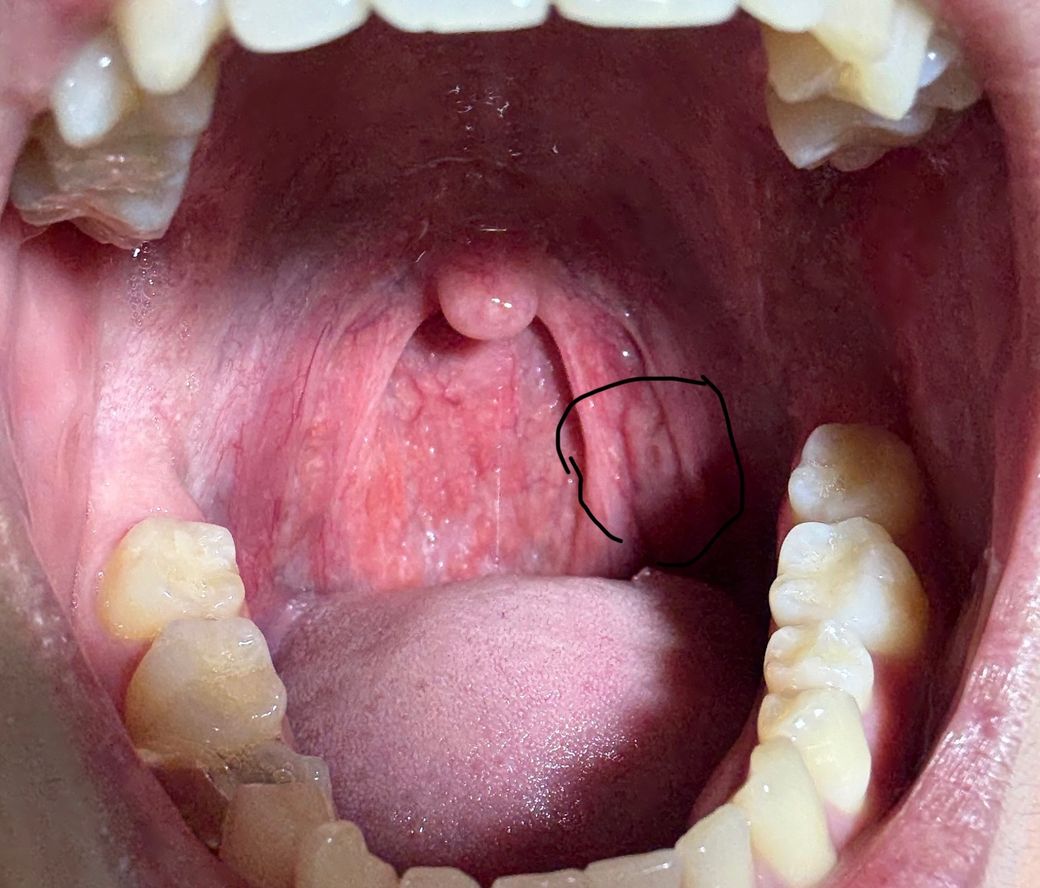

사진상 우측 편도부분 편도암 의심가는지 확인가능할까요

평소 편도가 자주 부어있고 편도염도 잦긴합니다. 하지만 사진상 우측에 있는 편도 부분이 비대칭처럼 육안상 부어있습니다.그리고 작은 여드름처럼 뭔가 있습니다.과거에는 이런적 없었고 비대칭처럼 된지 몇개월 지났습니다. 딱히 커지는지는 모르겠습니다만, 편도암 의심가는 양상일까요? 과거 이비인후과 내원했을때는 대충 보시더니 별거 아니라고 하셨습니다만, 문제있으면 다시 내원하려고합니다.

• 2번 째 사진

사진상 편도선으로 의심되는 부위의 점막의 불규칙한 표면 변화가 관찰되지만 편도암에서 관찰되는 종괴나 궤양성 병변이 아니므로 편도암으로 보기는 어렵습니다. 평소 편도염의 재발로 인한 만성 편도염이 발생하였고 이로 인한 편도 점막의 변화로 판단됩니다. 크기나 모양의 변화가 없다면 좀 더 지켜보아도 되겠으며 육안 소견상 편도암이 의심되는 것은 아니므로 당장 추가 검사나 진료를 필요하지 않겠습니다.